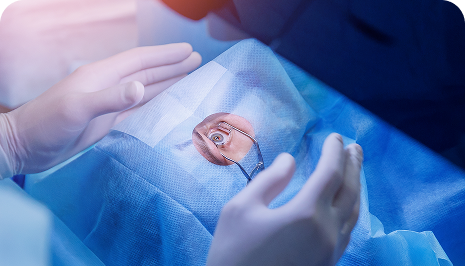

Cataract Surgery

What do you understand by Cataract? A cataract is an eye condition characterized by the clouding of the natural lens in the eye, leading to

Contoura Lasik

What is Contoura Vision? Contoura vision is a laser vision correction technique also called topography-guided LASIK surgery.

PRK Surgery

What is Photorefractive Keratectomy? Photorefractive keratectomy is a type of laser eye surgery, that is used to treat